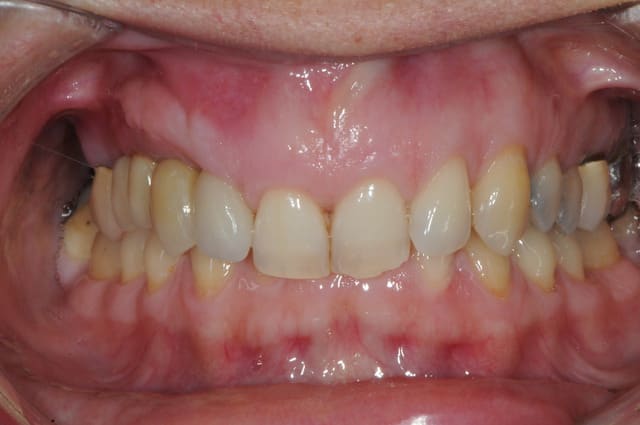

suite

exposition membrane; ça arrive, mais c'est pas grave.

pose implants

cicatrisation gingivale

mise à jour et aménagement tissulaire type Palacci

modification des collets et des bords libres

prise empreinte

piliers

couronnes...